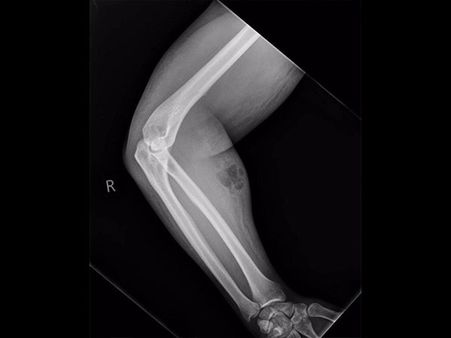

The Doctors Took An X-ray

Seeing the man's arm in a weird shape, the doctors decided to perform an X-ray. The semen had leaked into his soft tissue that caused the nasty infection. The semen injections that he had been taking as a once-a-month dose had apparently leaked into his soft tissue that caused the nasty infection. Due to this, he had developed cellulitis, a bacterial infection of the skin.